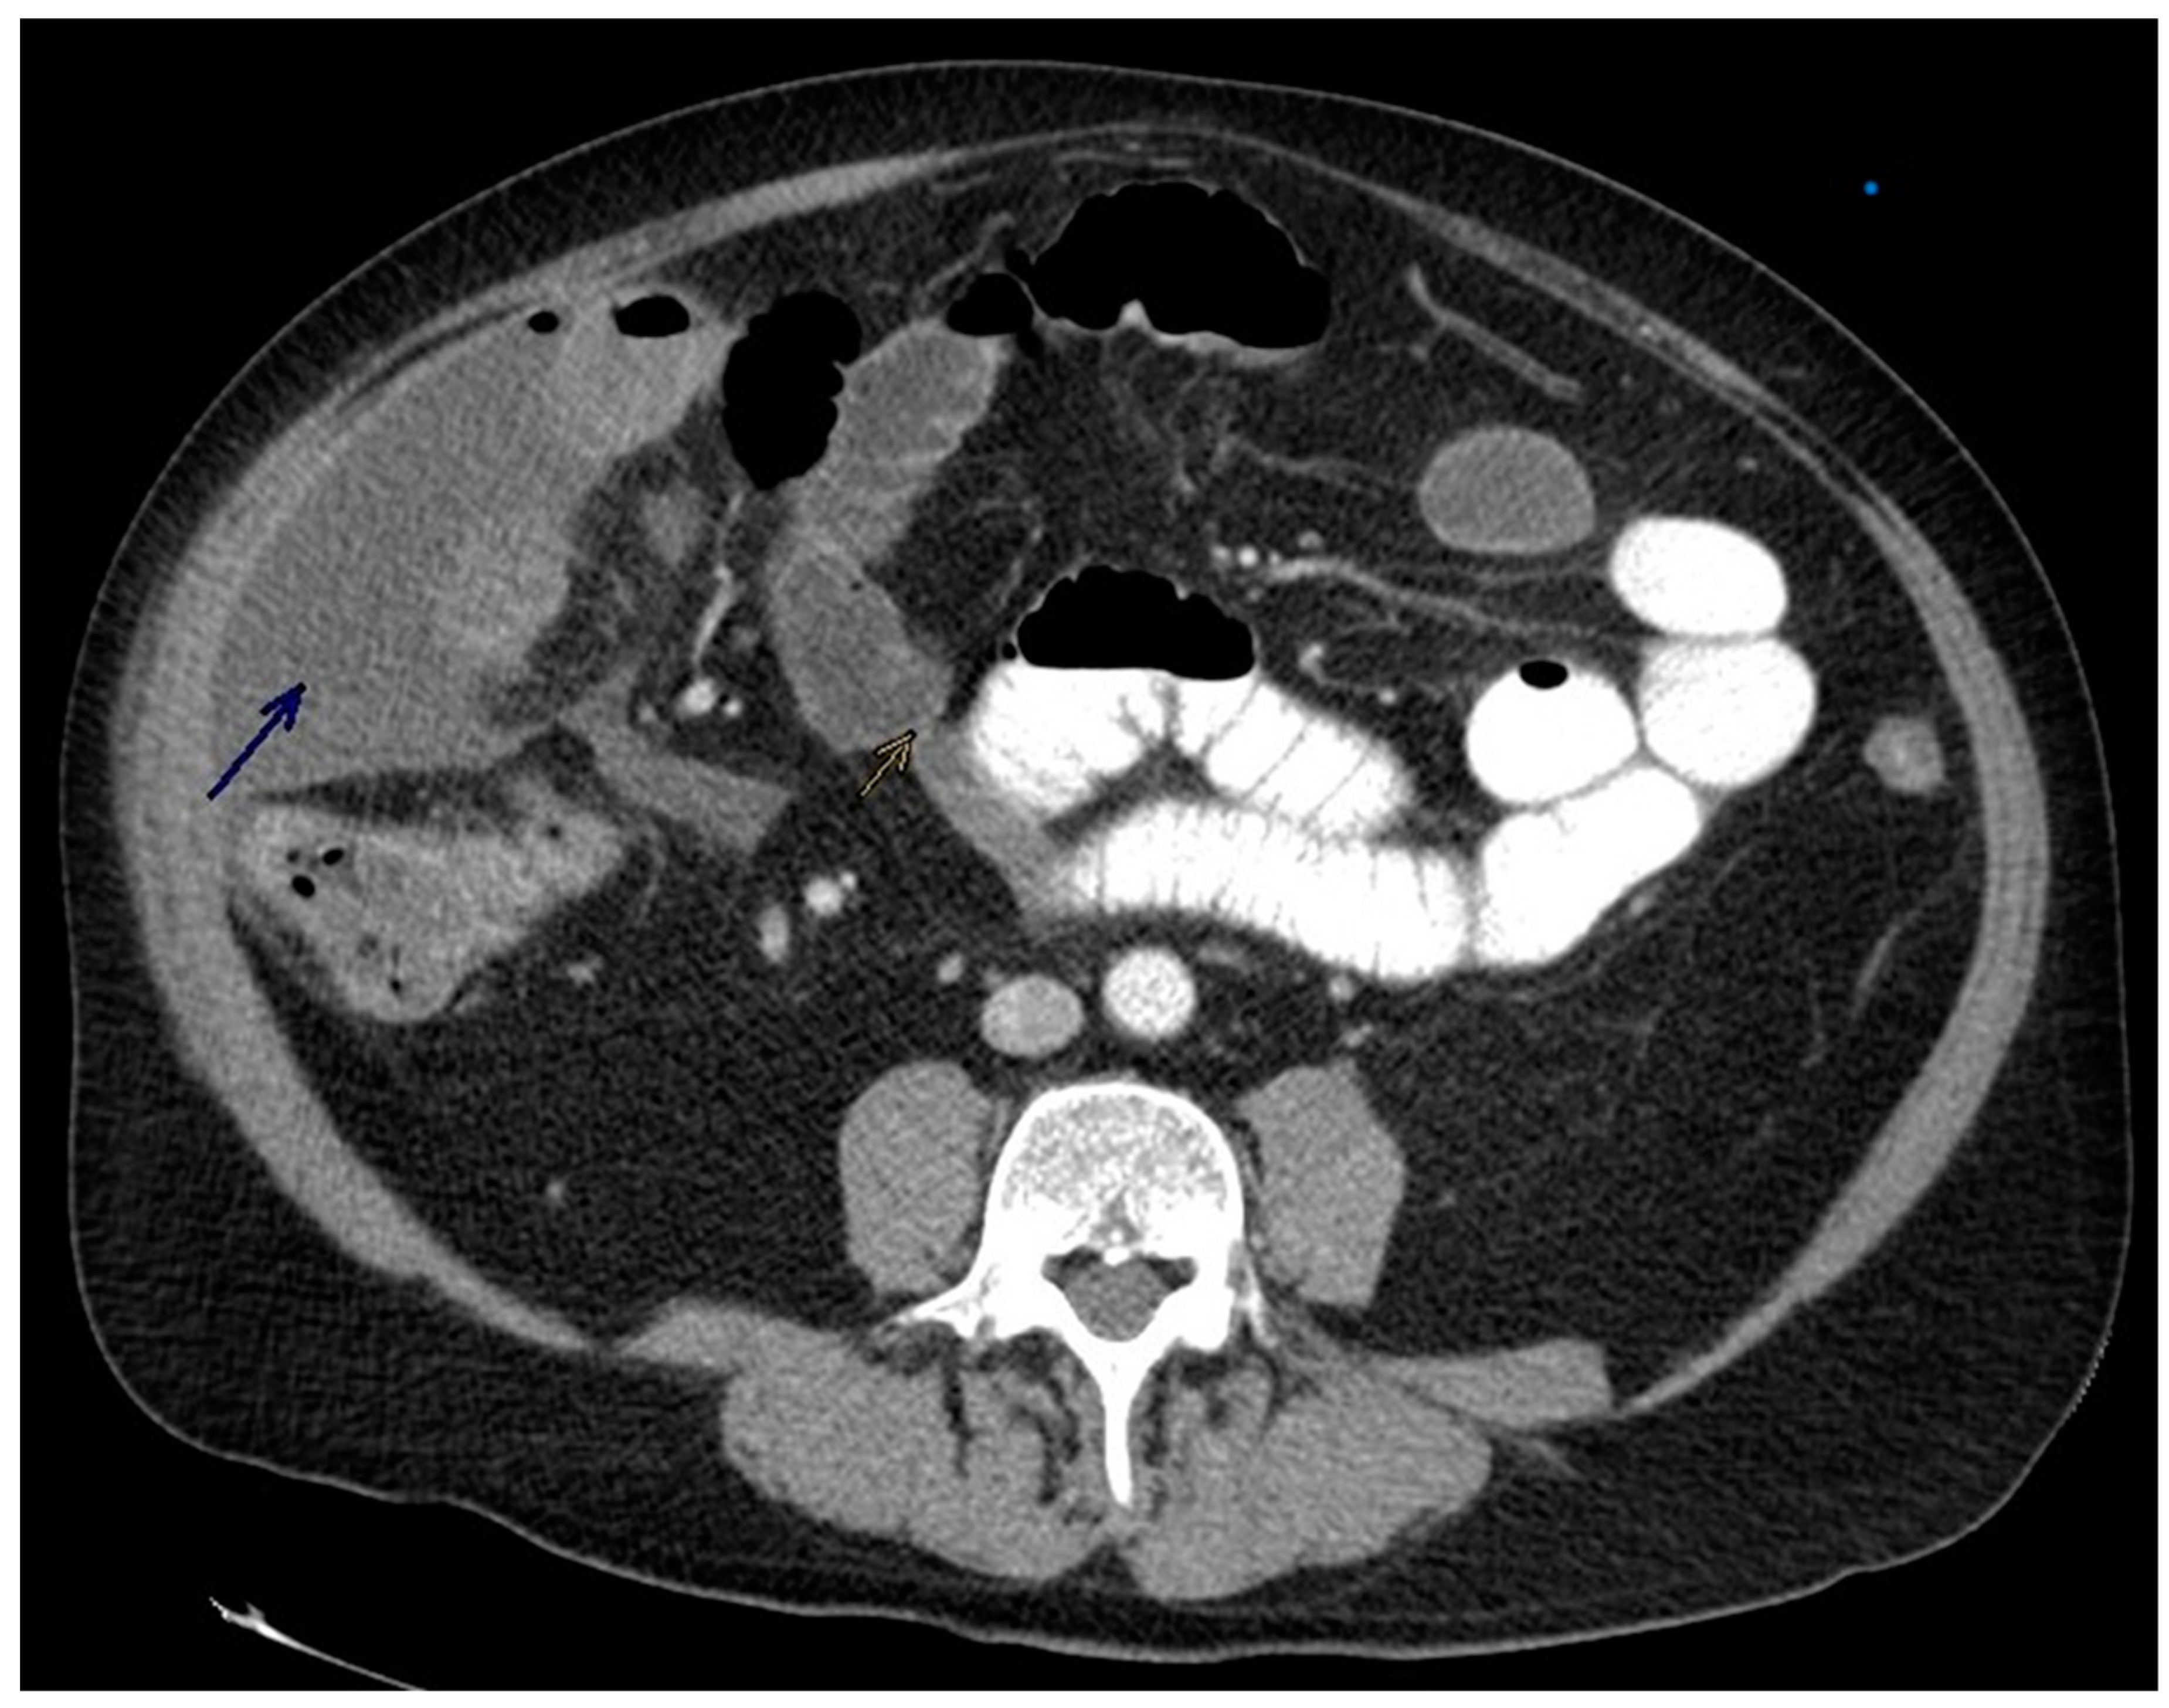

A 66-year-old male presented to the emergency department with 4 days of sudden-onset, intractable right lower quadrant pain associated with nausea and vomiting. Laboratory values were significant for leukocytosis of 12 cells/mm3 (reference 4-11.2), hyponatremia of 129 mmol/L (reference 136-145), and acute kidney injury with blood urea nitrogen (BUN) 38 mg/dL (reference 7-18) and creatinine 1.52mg/dL (reference 0.7-1.3). Vitals were stable on admission. Past medical history was significant for Schizophrenia for which he claimed compliance with oral ziprasidone 100mg twice daily. Initial imaging with CT abdomen/pelvis without contrast demonstrated narrowing of the ascending colon, possibly due to the presence of a mass. Surrounding layering free fluid with a few small foci of air within a collection measuring approximately 5.1 x 10.8 x 16.3 was demonstrated, as seen in Figure 1 below.

Figure 1. Computed Tomography of Abdomen with contrast. Blue Arrow pointing to layering free fluid foci with apical pockets of air surrounding the ascending colon and yellow arrow pointing to the stricture caused by the cancer.